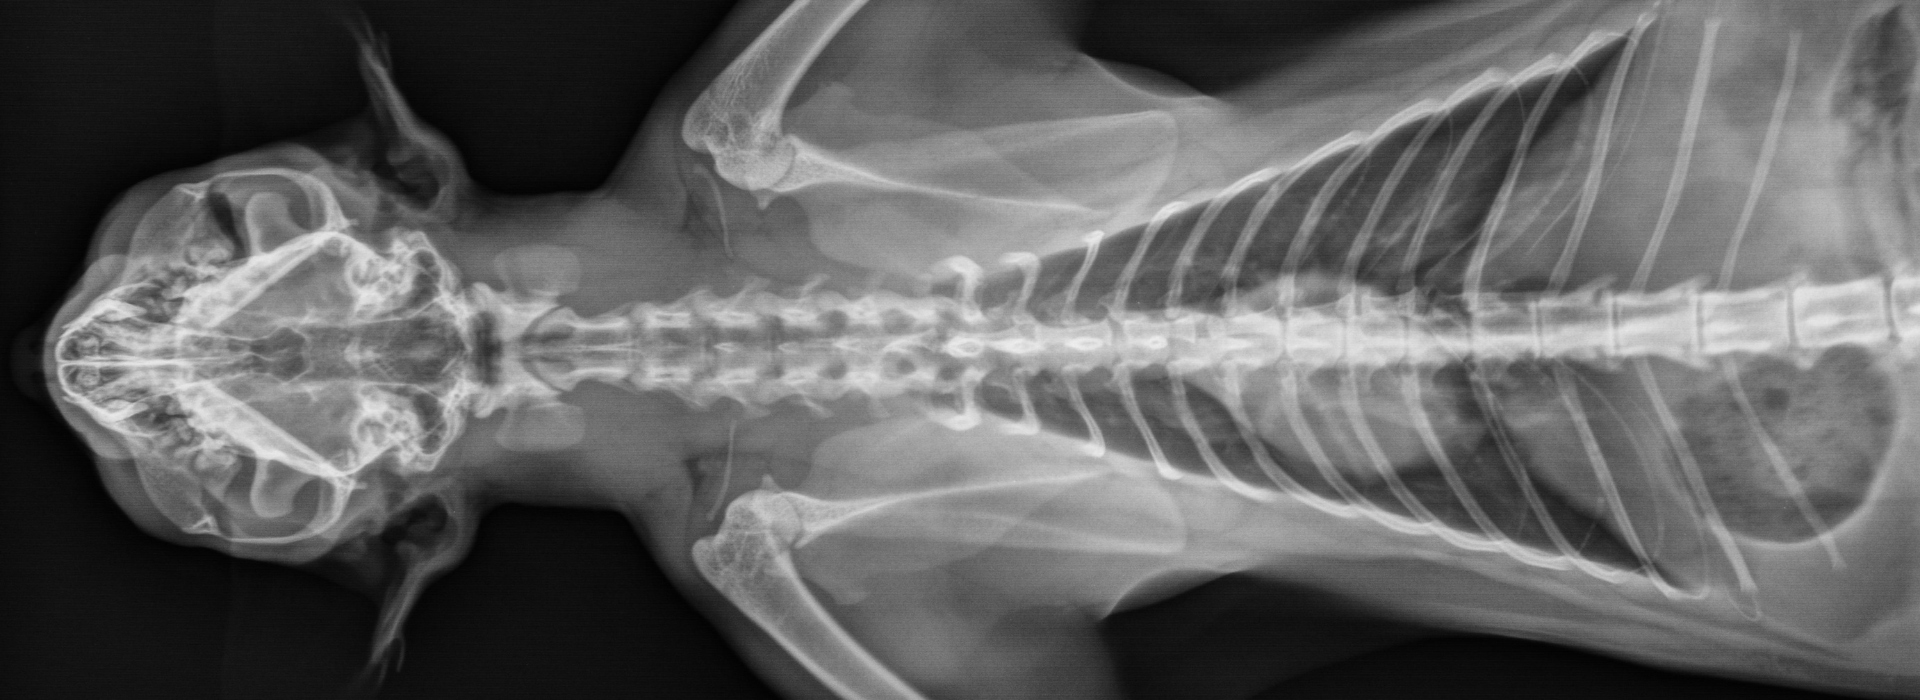

צילומי רנטגן הם בדיקה מהירה ולא פולשנית, המאפשרת לווטרינר לראות את המבנה הפנימי של העצמות והרקמות הצפופות בגוף. הם אמנם מזוהים עם שברים, אך השימושים שלהם נרחבים בהרבה:

• אבחון בעיות אורתופדיות: רנטגן הוא הכלי המרכזי לאבחון מצבים כמו דלקת פרקים, דיספלזיה של מפרק הירך או בעיות מפרקים אחרות, גם בשלבים מוקדמים.

• הערכת איברים פנימיים: ניתן לבדוק את הגודל, הצורה והמיקום של הלב, הריאות ואיברים פנימיים אחרים, ולזהות שינויים המעידים על בעיות כרוניות.

רנטגן לחתול